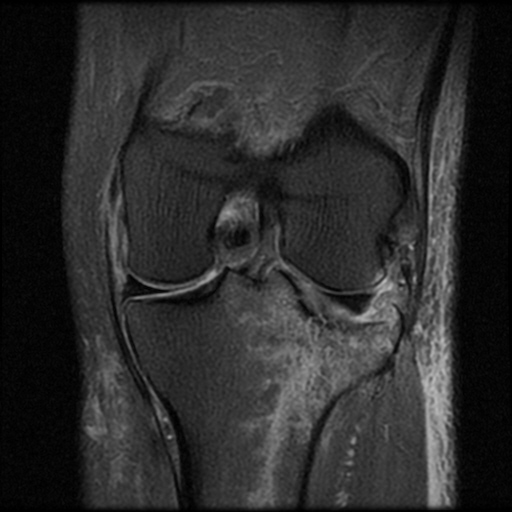

ÀÚ±â°ø¸í°Ë»ç

°æ°ñ ¿ÜÃøºÎ ¾Ð¹Ú°ñÀýÀÌ °üÂûµÊ(»çÁø 8, 9, 10)